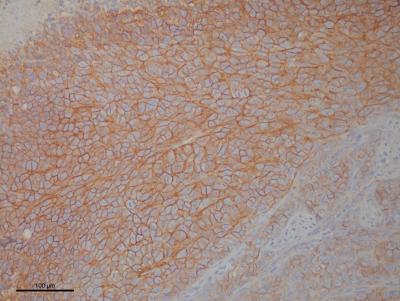

The researchers chose a druggable target protein, CD99, which is significantly expressed in Ewing sarcoma cells. CD99 is a transmembrane protein - one end sticks out on the cancer cell surface and the other end is inside of the cell. In fact, making an Ewing sarcoma diagnosis depends on both the appearance of the cell under the microscope and the fact that these cells express CD99 protein. Investigators don't know exactly what CD99 does but earlier research using experimental monoclonal antibodies that bind on to, and inhibit, CD99 stopped tumor growth in laboratory models.